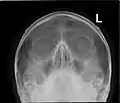

X-ray images and illustrations

Paranasal sinuses radiograph (occipitofrontal)